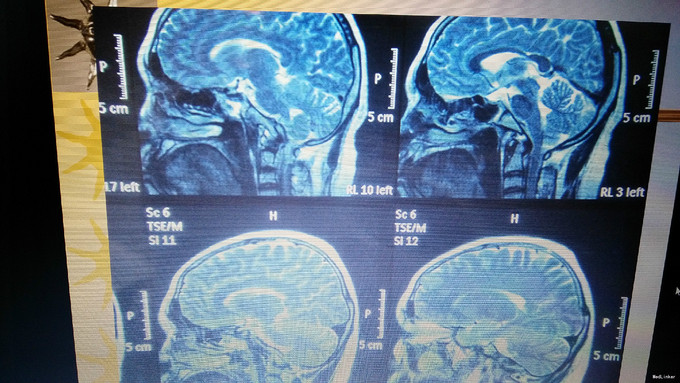

主诉:口渴多饮多尿35年,无月经来潮 现病史:患者6岁时无明显诱因出现口渴,大量饮水,多尿,曾在我院儿科就诊,诊断为“尿崩症”,给予垂体后叶素治疗,症状可好转,但患者未继续复查治疗,饮水量多于正常人每日饮水量。患者青春期时第二性征发育不明显,无月经来潮。20岁时于当地医院就诊,给予“黄体酮”治疗,可出现月经,量少,持续2-3天。患者未坚持服用药物,之后无月经出现。2年前开始多次出现鼻粘膜出血,量不详。患者有头痛、乏力症状,无头晕、视力模糊、无泌乳。

查体:乳房发育幼稚,乳晕浅,毛发稀疏,腋毛、阴毛无,眉毛稀疏。皮肤无瘀斑,眼睑轻度水肿 辅助检查:性腺轴:雌二醇96.50pmol/l,雌三醇<0.24nmol/l,孕酮<0.64nmol/l,FSH 0.92 mIU/ml, LH 0.17mIU/L 甲状腺轴:TSH 3.0433mIU/L, FT4 8.7700pmol/l,FT3 3.8100pmol/l 生长激素:0.20mIU/L,PRL:117.0mIU/L 肾上腺轴: 皮质醇(pg/ml) ACTH(mmol/l) 8:00 112.7 20.48 15:00 57.03 14.40 24:00 50.51 10.71 OGTT-OGIRT-OGCPRT 0分 30分 60分 120分 180分 葡萄糖(mmol/l)4.67 8.96 8.78 4.27 2.18 C肽(pmol/l) 1775.7 2496.9 6616.7 >6660.0 2939.8 胰岛素原(pg/ml)22.53 131.6 >200 198.20 21.03 患者无糖尿病,但存在胰岛素抵抗 ACTH兴奋实验: 12月17日 12月18日 ACTH(mmol/l) 皮质醇(pg/ml) ACTH(mmol/l) 皮质醇(pg/ml) 8:00 114.70 8.67 8:00 84.62 10.92 16:00 58.09 8.61 25单位ACTH泵空静点8小时 16:00 643.70 2000 12月19日 12月20日 ACTH(mmol/l) 皮质醇(pg/ml) ACTH(mmol/l) 皮质醇(pg/ml) 8:00 319.00 22.13 8:00 242.20 25.94 25单位ACTH泵空静点8小时 25单位ACTH泵空静点8小时 16:00 717 2000 16:00 843 2000

诊断:中心性肥胖(中度) 下丘脑综合征伴空泡蝶鞍综合征 治疗:患者垂体前叶功能减退,性腺轴计划给予人工月经治疗。